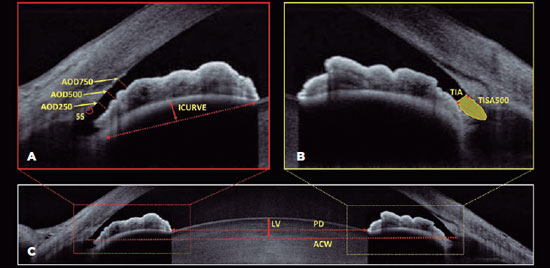

LPI

LPI was performed with Nd:YAG-laser (VISULAS YAG III, Carl Zeiss Meditec Inc.) after 15 min of pilocarpine 2% instillation(14,15). Laser was applied at the deepest and most peripheral pseudocrypt, preferably covered by the superior eyelid. Abraham’s lens was used to magnify the area where LPI was created. The power was titrated according to the tissular response starting at 5 mJ. Fluorometholone acetate 0.1% tid and brimonidine tartrate 0.2% bid were prescribed for 1 week. The patency of the ostium was verified by biomicroscopy and AS-OCT 2 weeks after the procedure (Figure 2).

11-fig02tb.jpg)

Lens vault measurement also presented a reduction after LPI (347 ± 171 µm vs. 301 ± 187 µm, p<0.001). Moreover, no significant change was observed in PD (4.23 ± 1.13 mm vs. 4.06 ± 0.93 mm, p=0.24). Figure 3 illustrates the changes in the anterior-chamber induced by LPI.

11-fig03tb.jpg)